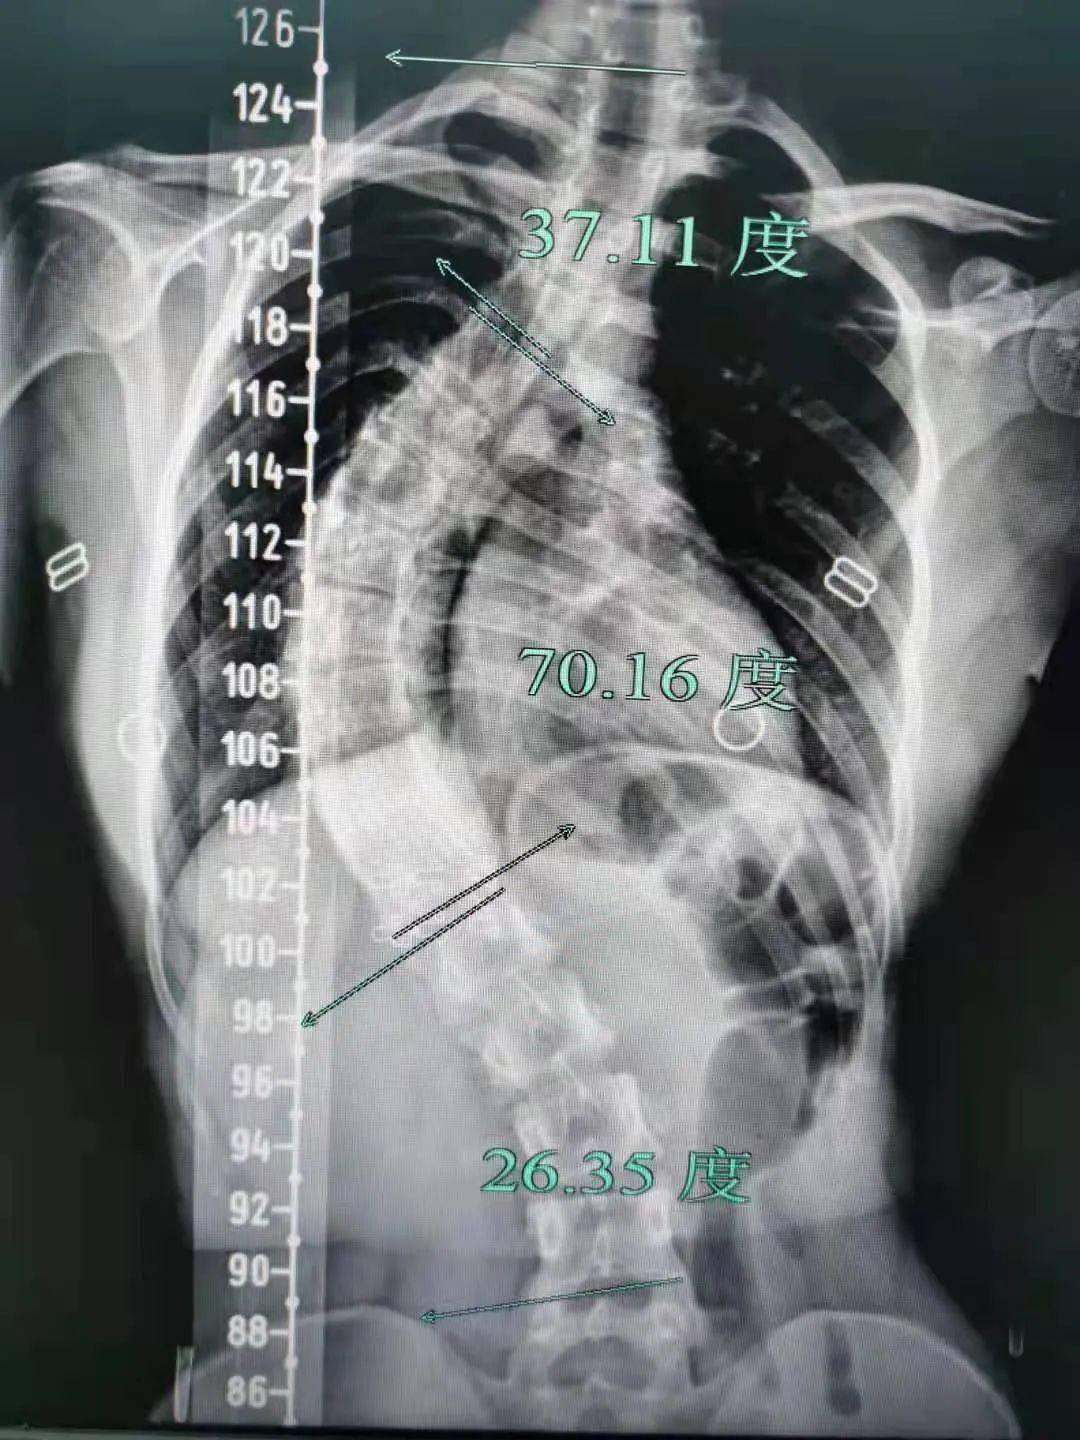

脊柱侧弯70度图片

脊柱侧弯70度成"s形",打入螺钉,截骨矫形终于挺直腰杆

女孩身体被折成70度专家提醒青少年需警惕脊柱侧弯